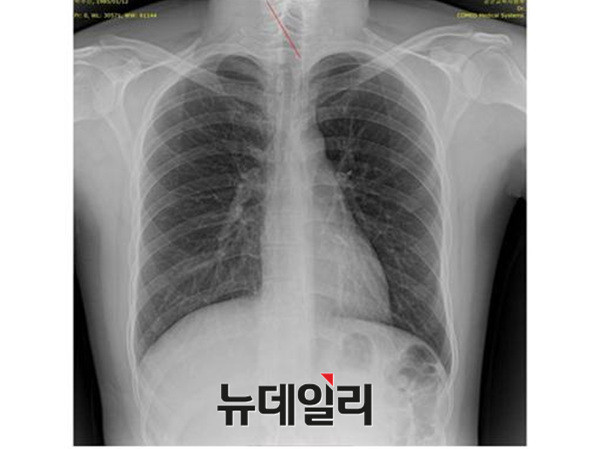

- ▲ 양승오 박사 재판 피고인들이, 박원순 시장 아들 주신씨 병역비리 의혹의 유력한 증거로 제시하고 있는 주신씨 명의의 엑스레이. 왼쪽부터 공군훈련소-자생병원-비자발급용 엑스레이. ⓒ 뉴데일리DB

외부 감정위원단이 판독할 주신씨 명의의 영상자료는 MRI 6장, 엑스레이 3장 등이다.

현재 피고인들은 주신씨 명의의 엑스레이 비교 판독 결과 나타나는 ①석회화 현상-②극상돌기 배열 방향-③흉곽의 모양-④기관(氣管)의 뻗은 모습 등을 근거로, 대리신검 혹은 영상자료 바꿔치기 가능성을 제기하고 있다.

이들 3개의 엑스레이는 모두 박주신씨의 신체를 촬영한 것으로 알려져 있기 때문에, 이들 엑스레이에 대한 판독결과 피사체를 동일인으로 볼 수 없는 유의미한 차이점이 발견된다면, 이는 박주신씨의 대리신검 혹은 영상자료 바꿔치기 의혹을 뒷받침하는 결정적 단서가 된다.

세계적 권위를 인정받은 영상의학전문의인 양승오 박사(동남권원자력의학원 암센터 핵의학과 주임과장)와 치과의사 김우현씨 등 박주신씨 병역비리 의혹을 주장해 온 시민들은, 위에서 언급한 3개의 엑스레이에 대한 비교 판독 결과, 이들 엑스레이를 같은 사람의 것으로 볼 수 없는 차이점을 발견하고 이를 재판부에 증거자료로 제출했다.